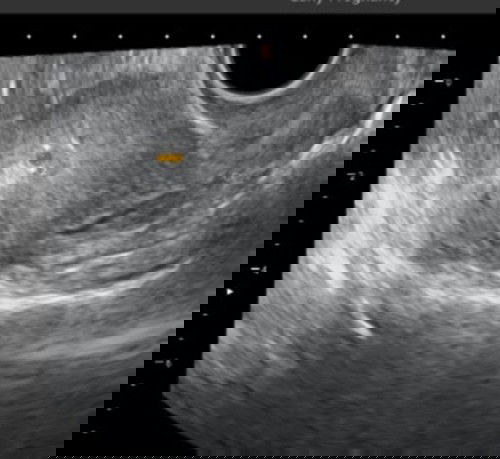

Hamil 5 minggu kantung baru terlihat 0,53 cm apakah normal?

Selamat siang bunda,mau brtnya ni bun siapa tau pengalamanny ada sama sprti saya, saat ini sya sdh telat 2 mnggu, hpht sya tgl 15 sept, sya usg transvaginal prtama stelah tp + tgl 20 okt hasilny trlihat pnebalan dinding rahim dan d ksh obat penguat microgest 200 mg d mnumny 2x sehari,dan vitamin, lalu usg kdua tgl 26 okt dan terlihat kantung ukuranny 0,53 cm via usg transvaginal, harusny saat itu udh usia ny 5 mngguan, tp klo lht dr hasil usg blm smpe 5 mnggu kata dokterny..apa ini termasuk normal y bun ukuranny saat itu hanya 0,53 cm sperti yg trlihat d foto usg ini? Dan apakah bunda ada yg pernah d ksh obt penguat microgest 200 mg d sruh minumny 2 kali sehari pagi sm malem? #bantusharing #sharingpengalaman